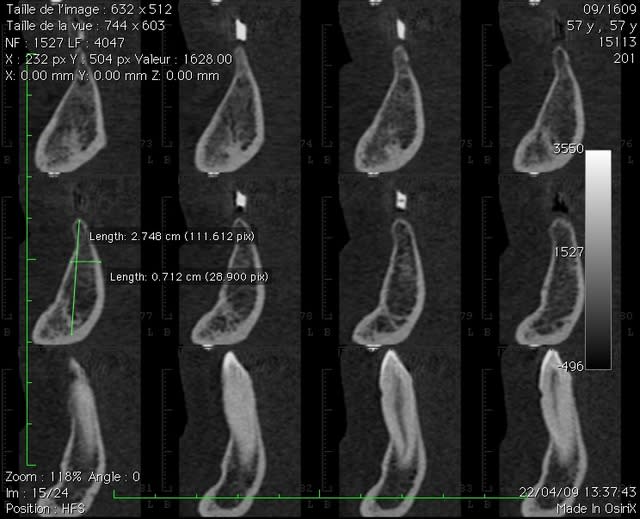

ce que je considère comme pas simple du tout expansion symphise.

ce fut long (pas loin de trois heures) mais bon!

3 h car je laisse l'os travailler , il faut qu'il "s'ecarte" lentement sinon craque.

pas du D1, sans fenetre laterale ça ne marcherais pas, par contre fin.